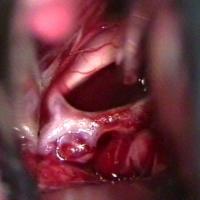

Als Vorgeschmack einige Bilder zum zukünftigen Inhalt: